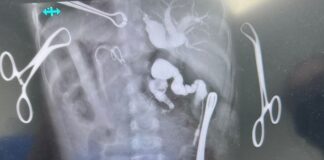

Reconstruye HGZ No. 71 del IMSS Veracruz Norte vía biliar...

• Para tal efecto, se utilizó un segmento del intestino